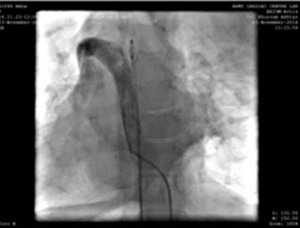

Puncture of the left jugular vein, and 5F angiography catheter, showing the upper arm vein - superior vena cava - right atrium connection path.

We used a 9F delivery sheath, which was advanced over and placed in the descending aorta over the super-stiff guidewire. A MemoPartTM cone shape PDA occluder 14/12 mm, was attached to the delivery cable and progressed across the delivery sheath. The placement of the occlude was proper with no residual flow.